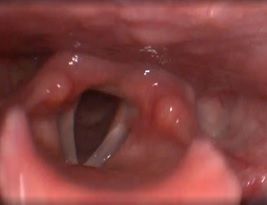

Клинический пример №1. Удаление папиллома правой голосовой складки с использованием СО-2 лазера.

После операции воспалительные проявления со стороны голосовой складки едва заметны.

Рис 1А Папиллома правой голосовой складки. До операции.

Рис 1Б. Папиллома правой голосовой складки. 1 сутки после операции